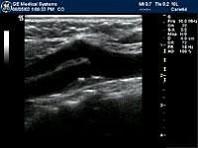

根据颈部动脉声像图初步诊断?(?)A.颈部动脉内血栓B.颈部动脉内肿瘤C.颈部动脉粥样斑块D.颈部动脉内膜局限增厚E.大动脉炎

问题 根据颈部动脉声像图初步诊断?(?)

选项 A.颈部动脉内血栓 B.颈部动脉内肿瘤 C.颈部动脉粥样斑块 D.颈部动脉内膜局限增厚 E.大动脉炎

答案 C